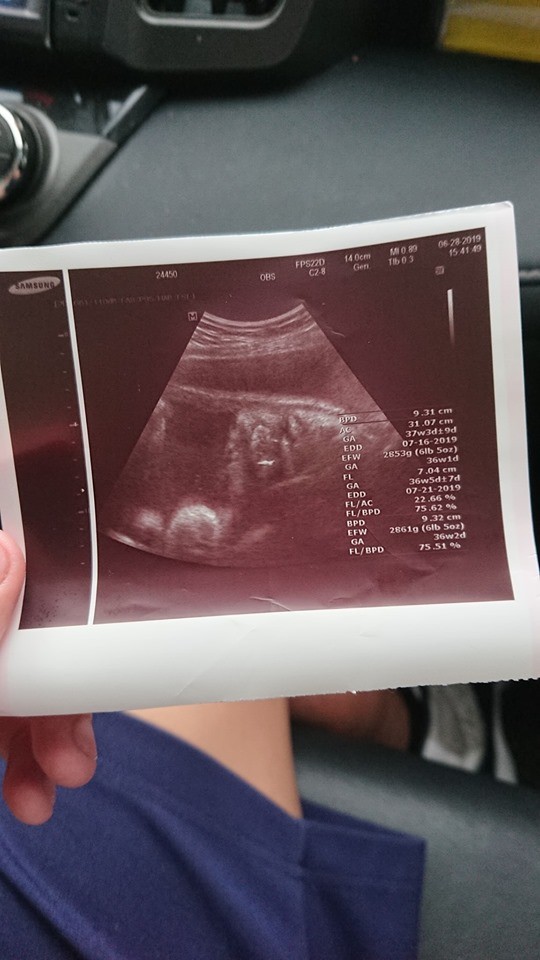

▼帶著他們到婦產科產檢後,醫生告知「胎兒是男孩,已經37週大,預產期在7月中」。為了保險起見,7月1日他們再帶女方去大醫院檢查,沒想到醫生竟表示「已經開2指,今晚或明天早上就會生」!